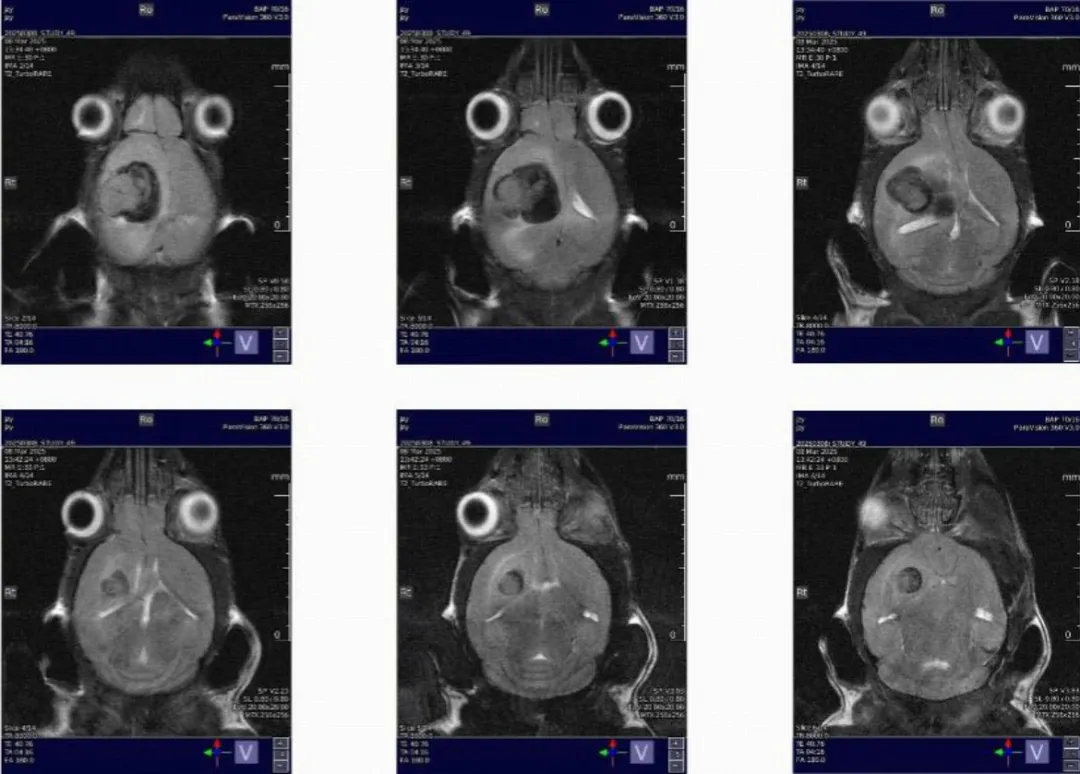

脑部成像:

T2WI清晰显示灰质(稍高)、白质(稍低)、脑脊液(高信号);3D-TOF可清晰显示脑动脉。

活体扫描需麻醉,虚弱动物单次扫描建议≤30分钟。